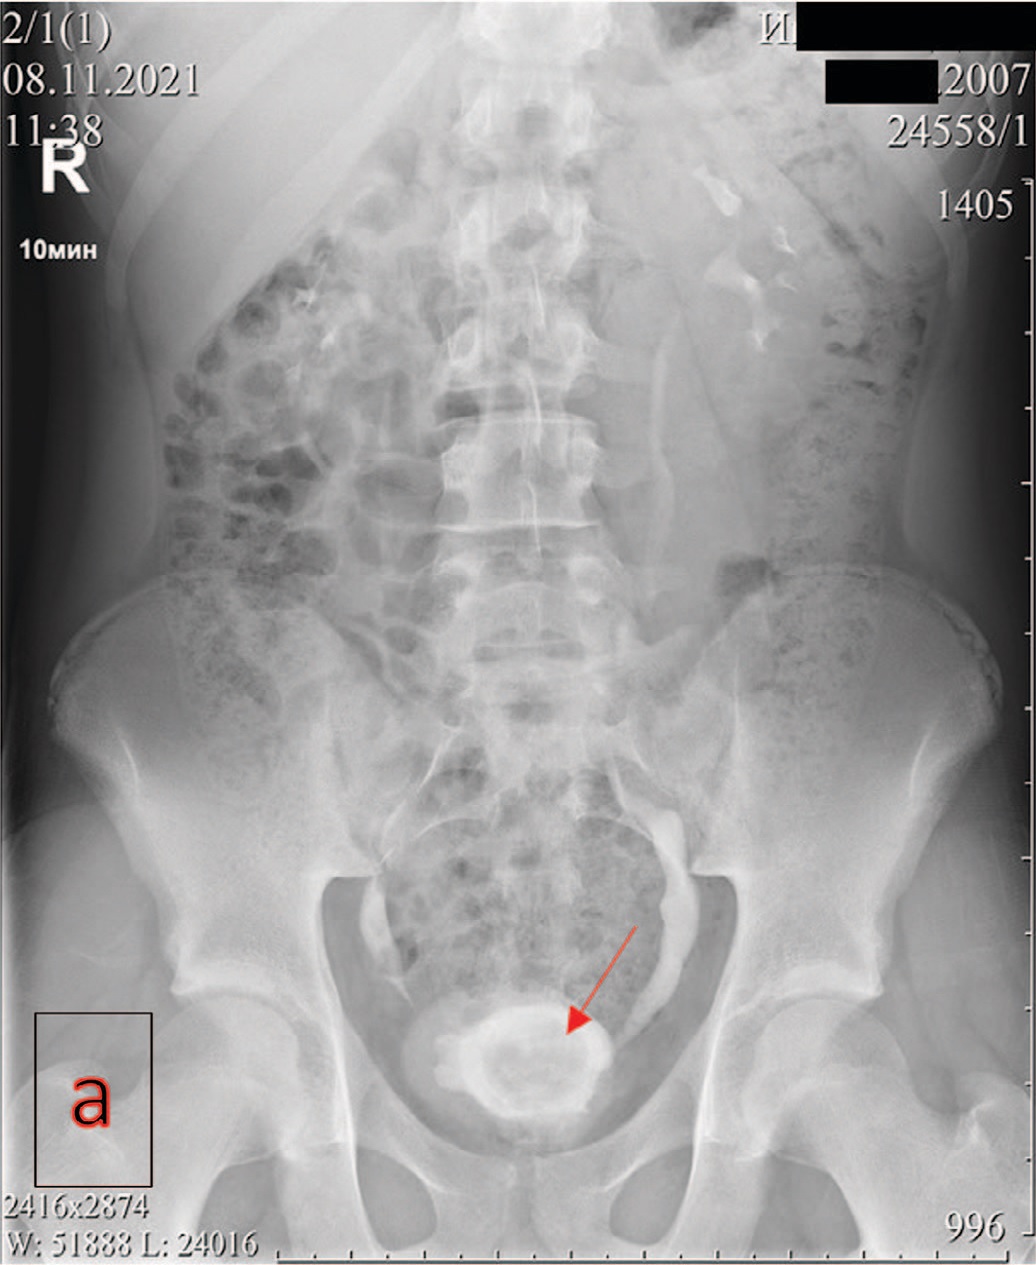

Экскреторная урография при нефроптозе: диагностические изображения